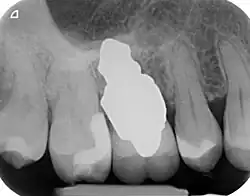

RAIs are custom made to perfectly fit the tooth socket of a specific patient immediately after tooth extraction. Therefore every implant is unique. As an optimised root-form it is much more than a simple 1:1 replica of a tooth. Since it exactly fills the gap left after the tooth is extracted, surgery is rarely needed. The implant can be produced from a copy of the extracted tooth, an impression of the tooth socket, or from a CT scan or CBCT scan.[7] The advantage of a CBCT scan is that the implant can be produced before extraction. With the former methods, it takes one or two days to fabricate an implant.

A root analogue implant can be fabricated from zirconium dioxide (zirconia) or titanium.[8] Successful titanium RAIs have been three-dimensionally printed as porous one-piece implants, using CAD software.[9] However, zirconia is the preferred material, because it is more esthetic in colour, with no grey discolouration visible through gums.[10][5]